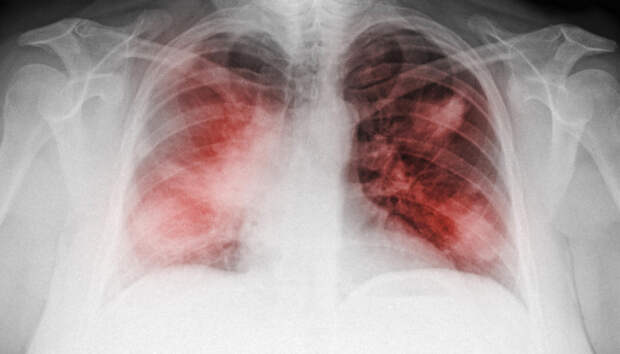

Всем пациентам с воспалением легких неоднократно проводится исследование на COVID-19 Семнадцать человек за сутки госпитализированы с внебольничной пневмонией в Карелии, сообщает оперштаб по борьбе с распространением коронавирусной инфекции. Летальных исходов за прошедшие 24 часа в республике не зафиксировано.

Начиная с 1 апреля, с внебольничной пневмонией госпитализированы 1835 пациентов, 85 человек умерли (с учетом пациентов, госпитализированных […] The post Больные с пневмонией продолжают поступать в больницы Петрозаводска first appeared on Информационное Агентство 365 дней.